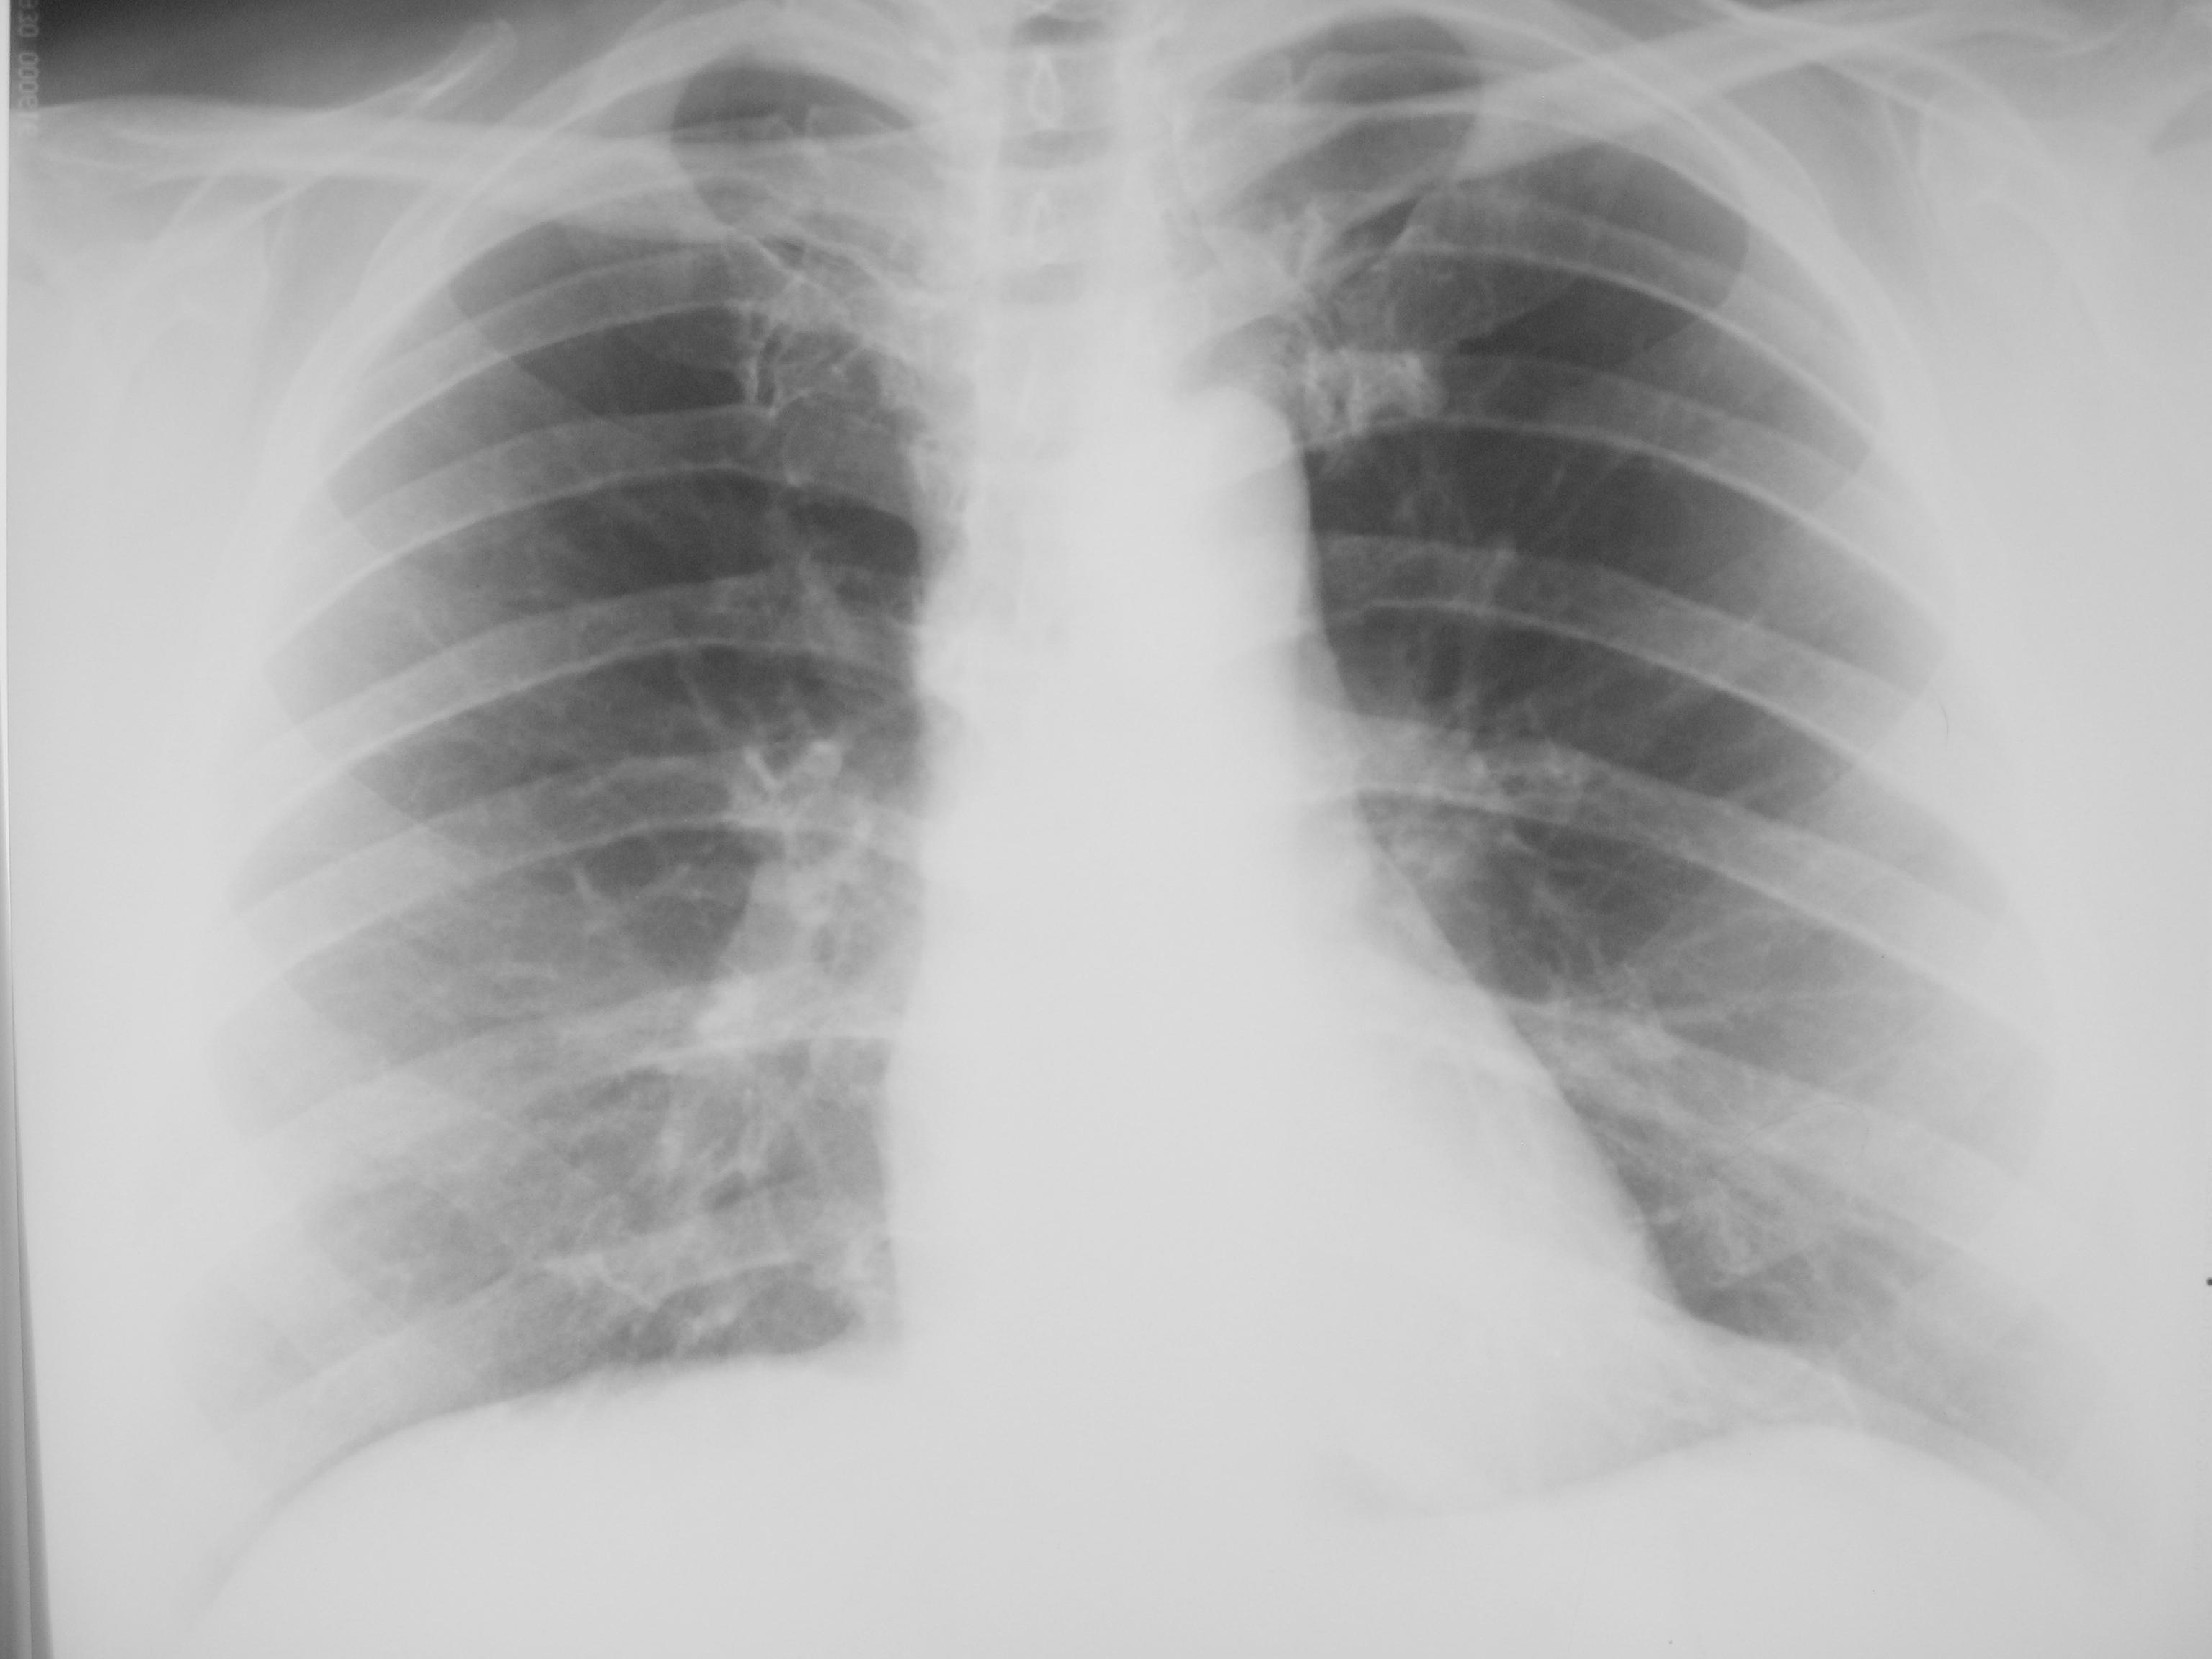

Пациентке около 70 лет, некоторое время назад была госпитализирована по поводу ущемленной грыжи, на р-графии ОГК - подозрение на центр рак правого легкого (в выписке только заключение), снимков на руках нет, рекомендовано обследование по м\ж. Сегодняшние снимки. Я никакой патологии, кроме пневмосклероза, не нахожу. А Вы, уважаемые коллеги?

Возможно, не очень хорошо сфотографировала, есть усиление и деформация легочного рисунка. В принципе, здесь это не так важно. Хотя, вообще, это интересная тема, замечала, что некоторые коллеги (в офф-лайне) ставят диагноз эмфизема, пневмосклероз, оттакливаясь от возраста больного.

Если на рентгенограмме норма, то зачем придумывать велосипед. Здесь нет ни намека на центральный рак

А я и признаков пневмосклероза не нахожу и эмфиземы признаков тоже не наблюдаю.)

Ну да, без снимков на руках, только по заключению сразу засовывать в пациентку бронхоскоп это конечно отличное обследование. Указаний на то что у пациентки есть кровохаркание или клиника нет, заключение дано на основании снимка в стационаре, при повторном снимке почти голубая норма - так зачем человеку бронхоскопия, действительно можно успокоить пациентку и отпустить